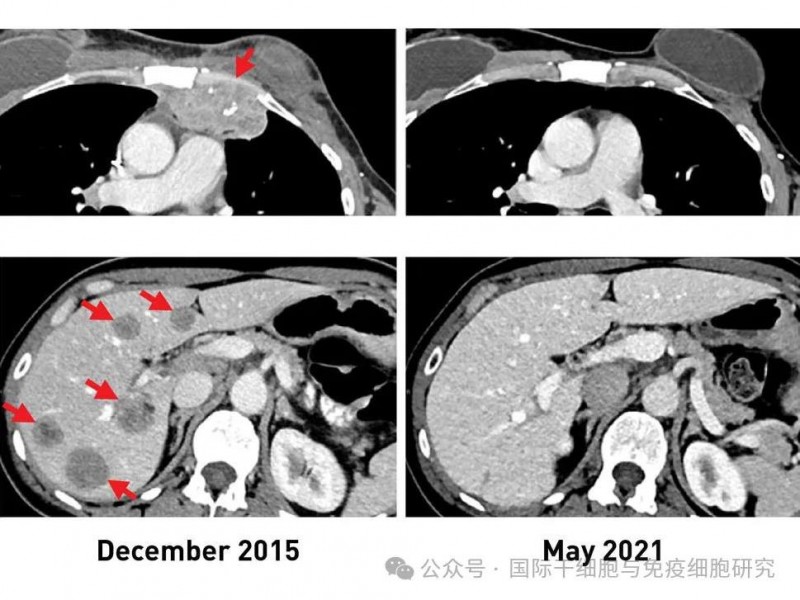

值得一提的是,其中1例转移性乳腺癌患者,在治疗前,其肝脏(左下)、胸壁(左上)均可见转移性病变。入组接受TIL细胞治疗后,肿瘤完全缩小,换言之,她幸运地获得了完全缓解(CR)!而且治疗5年后复查影像学显示,至今仍未患癌症。

▲图源“NCI”,版权归原作者所有,如无意中侵犯了知识产权,请联系我们删除